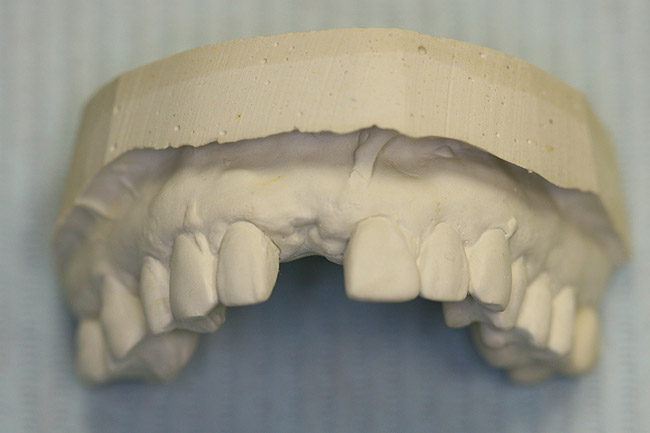

Figure  17  A diagnostic and/or treatment wax-up is fabricated.

Figure 17

Figure 18  A diagnostic and/or treatment wax-up is fabricated.

Figure 18